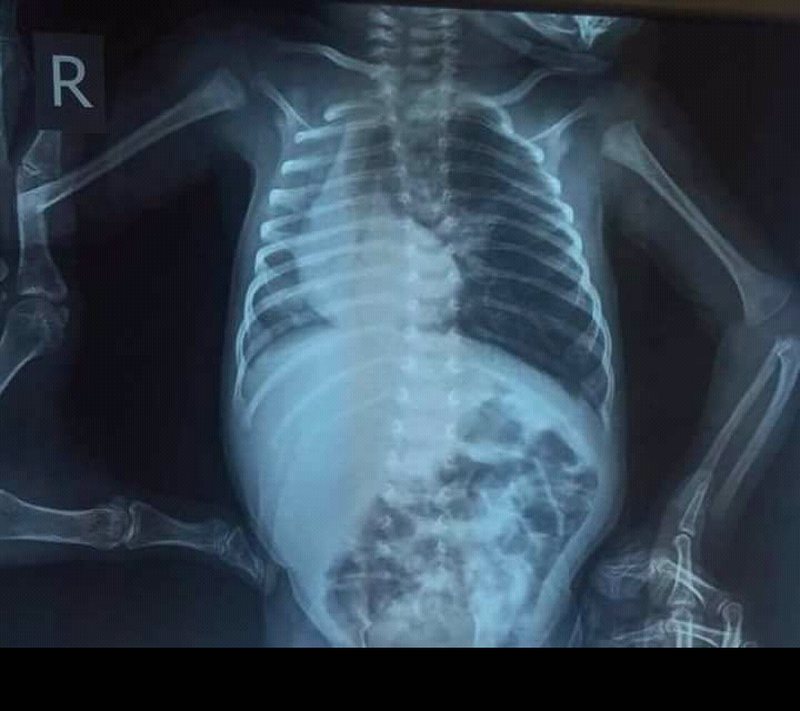

Dextrocardia is a rare congenital condition in which the apex of the heart is located on the right side of the body.There are two main types of dextrocardia: dextrocardia of embryonic arrest and dextrocardia situs inversus. 1.Dextrocardia of embryonic arrest In this form of dextrocardia, the heart is simply placed further right in the thorax than is normal. It is commonly associated with severe defects of the heart and related abnormalities including pulmonary hypoplasia. 2.Dextrocardia situs inversus Dextrocardia with situs inversus refers to the heart being a mirror image situated on the right side. For all visceral organs to be mirrored, the correct term is dextrocardia situs inversus totalis. Although statistically people with dextrocardia do not have any medical problems from the disorder, they may be prone to a number of bowel, esophageal, bronchial and cardiovascular disorders (such as double outlet right ventricle, endocardial cushion defect and pulmonary stenosis).Certain cardiovascular and pulmonary disorders related to dextrocardia can be life-threatening if left unchecked. Kartagener syndrome may also be present in patients with dextrocardia but this must be in the setting of situs inversus and may include male infertility.

Triad of kartageners syndrome is situs inversus bronchiectasis and sinusitis